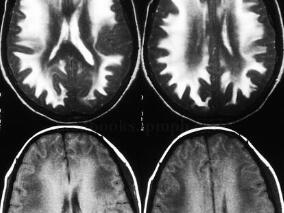

1小时条评论女性,14岁,汉族,右利手。 主诉:言语欠流利2年,右侧肢体活动不灵活3个月。 病史:患者于2年前无明显诱因下出现言语不流利,讲话速度较前变慢,有时词语含糊,但基本能正常表达意思,家人未予特别注意。1年前家人发现患者学习成绩逐渐下降,各科考试勉强能及格...